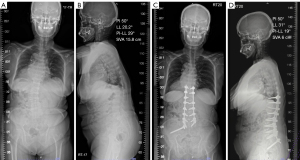

The 2-year postoperative fusion rate was 95% (76/80) (Table 3). The overall complication rate was 21% (17 patients), including four cases of S1 screw loosening, two cases of PJK, six cases of rod breakage (Figure 2) and three cases of S2AI screw-related pain. Two re-operations (3%) were performed due to rod breakage (Figure 3), resulting from loss of reduction following the fracture.

In our study, the reoperation rate was 3%, which is similar to a study by Martin et al. where 5% of patients (6/125) required reoperation due to acute failure of S2AI screws within 6 weeks postoperatively (20). Martin et al. also found that changes in LL were statistically significantly greater in the failure group compared to the non-failure group. Additionally, Ha et al. reported that 9.6% of patients experienced S2AI screw-related pain, and 3.4% required a second operation for screw removal (9). In contrast, our study had no cases of reoperation due to screw-related pain. However, two patients required re-operative surgery due to loss of reduction following rod fracture, which resulted in sagittal imbalance and intolerable back pain.